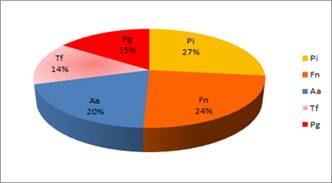

Proporción de los patógenos estudiados en los cuadros de Periodontitis Agresiva

Otra forma de analizar la importancia del microorganismo en el cuadro es estudiándolo en relación a la detección del resto de los patógenos estudiados. Si consideramos como una ocurrencia la detección de un determinado patógeno en un paciente, el 100% de ocurrencias estaría representado por el total de detecciones de los cinco patógenos estudiados. Al estudiar la proporción en que se presenta cada microorganismo en relación al resto de los microrganismos (al total de ocurrencias) se observan las siguientes proporciones (Graf. 5).

El microorganismo que apareció en mayor proporción fue P. intermedia, seguido de F. nucleatum. El tercer lugar correspondió a A. actinomycetemcomitans representando el 20%.

Aquí nuevamente los porcentajes están mayormente influenciados por el mayor número de casos localizados que generalizados.